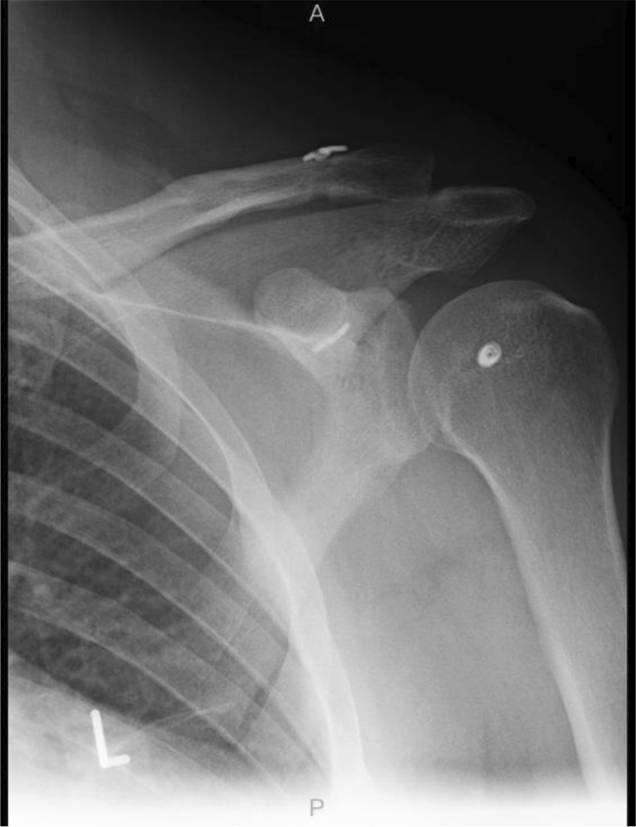

Ein 53-jähriger Patient stellt sich 9 Jahre nach ACG-Sprengung (Rockwood III), damals in Folge eines Sturzes beim Skifahren, jetzt mit erneuten Beschwerden in der linken Schulter vor. Es ist kein die Symptomatik erklärendes, adäquates Retrauma erinnerlich. Die Schmerzen treten dabei insbesondere bei sportlicher Betätigung auf. Die Versorgung der Verletzung erfolgte 2015 in Fadentechnik mit zwei DogBone-Buttons (Arthrex Inc., Naples, Florida, USA; Abb. 1).

Abb. 1

Röntgenaufnahme Schulter links a.‑p. 2015: korrekte Lage des Fadenmaterials und Button mit bereits partiellem Repositionsverlust